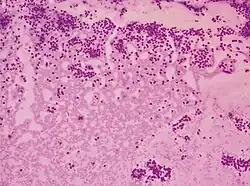

Category V with nuclear groove (arrow) Cytopathology suspicious for Hürthle cell neoplasm (Bethesda category IV, rather than Hürthle cell hyperplasia), Pap stain.[14]

Cytopathology suspicious for Hürthle cell neoplasm (Bethesda category IV, rather than Hürthle cell hyperplasia), Pap stain.[14]

- ↑ Image by Mikael Häggström, MD. References for findings:

- Ayana Suzuki, C.T., Andrey Bychkov, M.D., Ph.D. "Hürthle cell neoplasm". Pathology Outlines.{{cite web}}: CS1 maint: multiple names: authors list (link) Last author update: 7 May 2020. Last staff update: 12 May 2022

- Shawky M, Sakr M (2016). "Hurthle Cell Lesion: Controversies, Challenges, and Debates". Indian J Surg. 78 (1): 41–8. doi:10.1007/s12262-015-1381-x. PMC 4848220. PMID 27186039. - ↑ Renuka, I.V; Saila Bala, G; Aparna, C; Kumari, R; Sumalatha, K (December 2012). "The Bethesda System for Reporting Thyroid Cytopathology: Interpretation and Guidelines in Surgical Treatment". Indian J Otolaryngol Head Neck Surg. 64 (4): 305–311. doi:10.1007/s12070-011-0289-4. PMC 3477437. PMID 24294568.